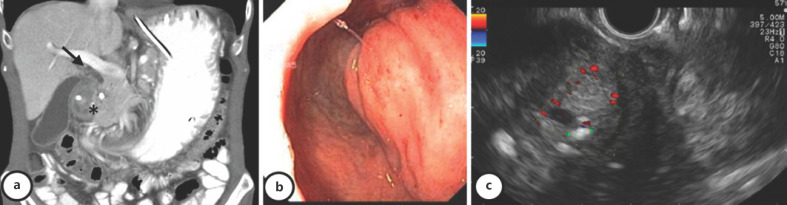

Introduction: Groove pancreatitis (GP) is a type of chronic segmental pancreatitis that affects the pancreatoduodenal groove area, and it is often misdiagnosed. Outflow obstruction of the minor papilla associated with alcohol consumption seems to be the main pathophysiological mechanism, and it affects mainly middle-aged males. Symptoms include nausea and postprandial vomiting from gastric outlet obstruction, weight loss, and abdominal pain. Despite modern advances, such as radiological and endoscopic methods, distinction between GP and pancreatic cancer remains a challenge, and histological examination is sometimes necessary. When a diagnosis can be obtained without a surgical specimen, management can be conservative in the absence of acute or chronic complications.

Case presentation: The authors present 2 clinical cases which portray the diagnostic workup and management decisions of this entity.

Discussion/conclusion: GP is a clinical entity, offering diagnostic and therapeutic challenges. Imaging exams are crucial in the diagnosis and follow-up, but surgery may be necessary in a significant number of cases due to the incapacity to rule out malignancy.